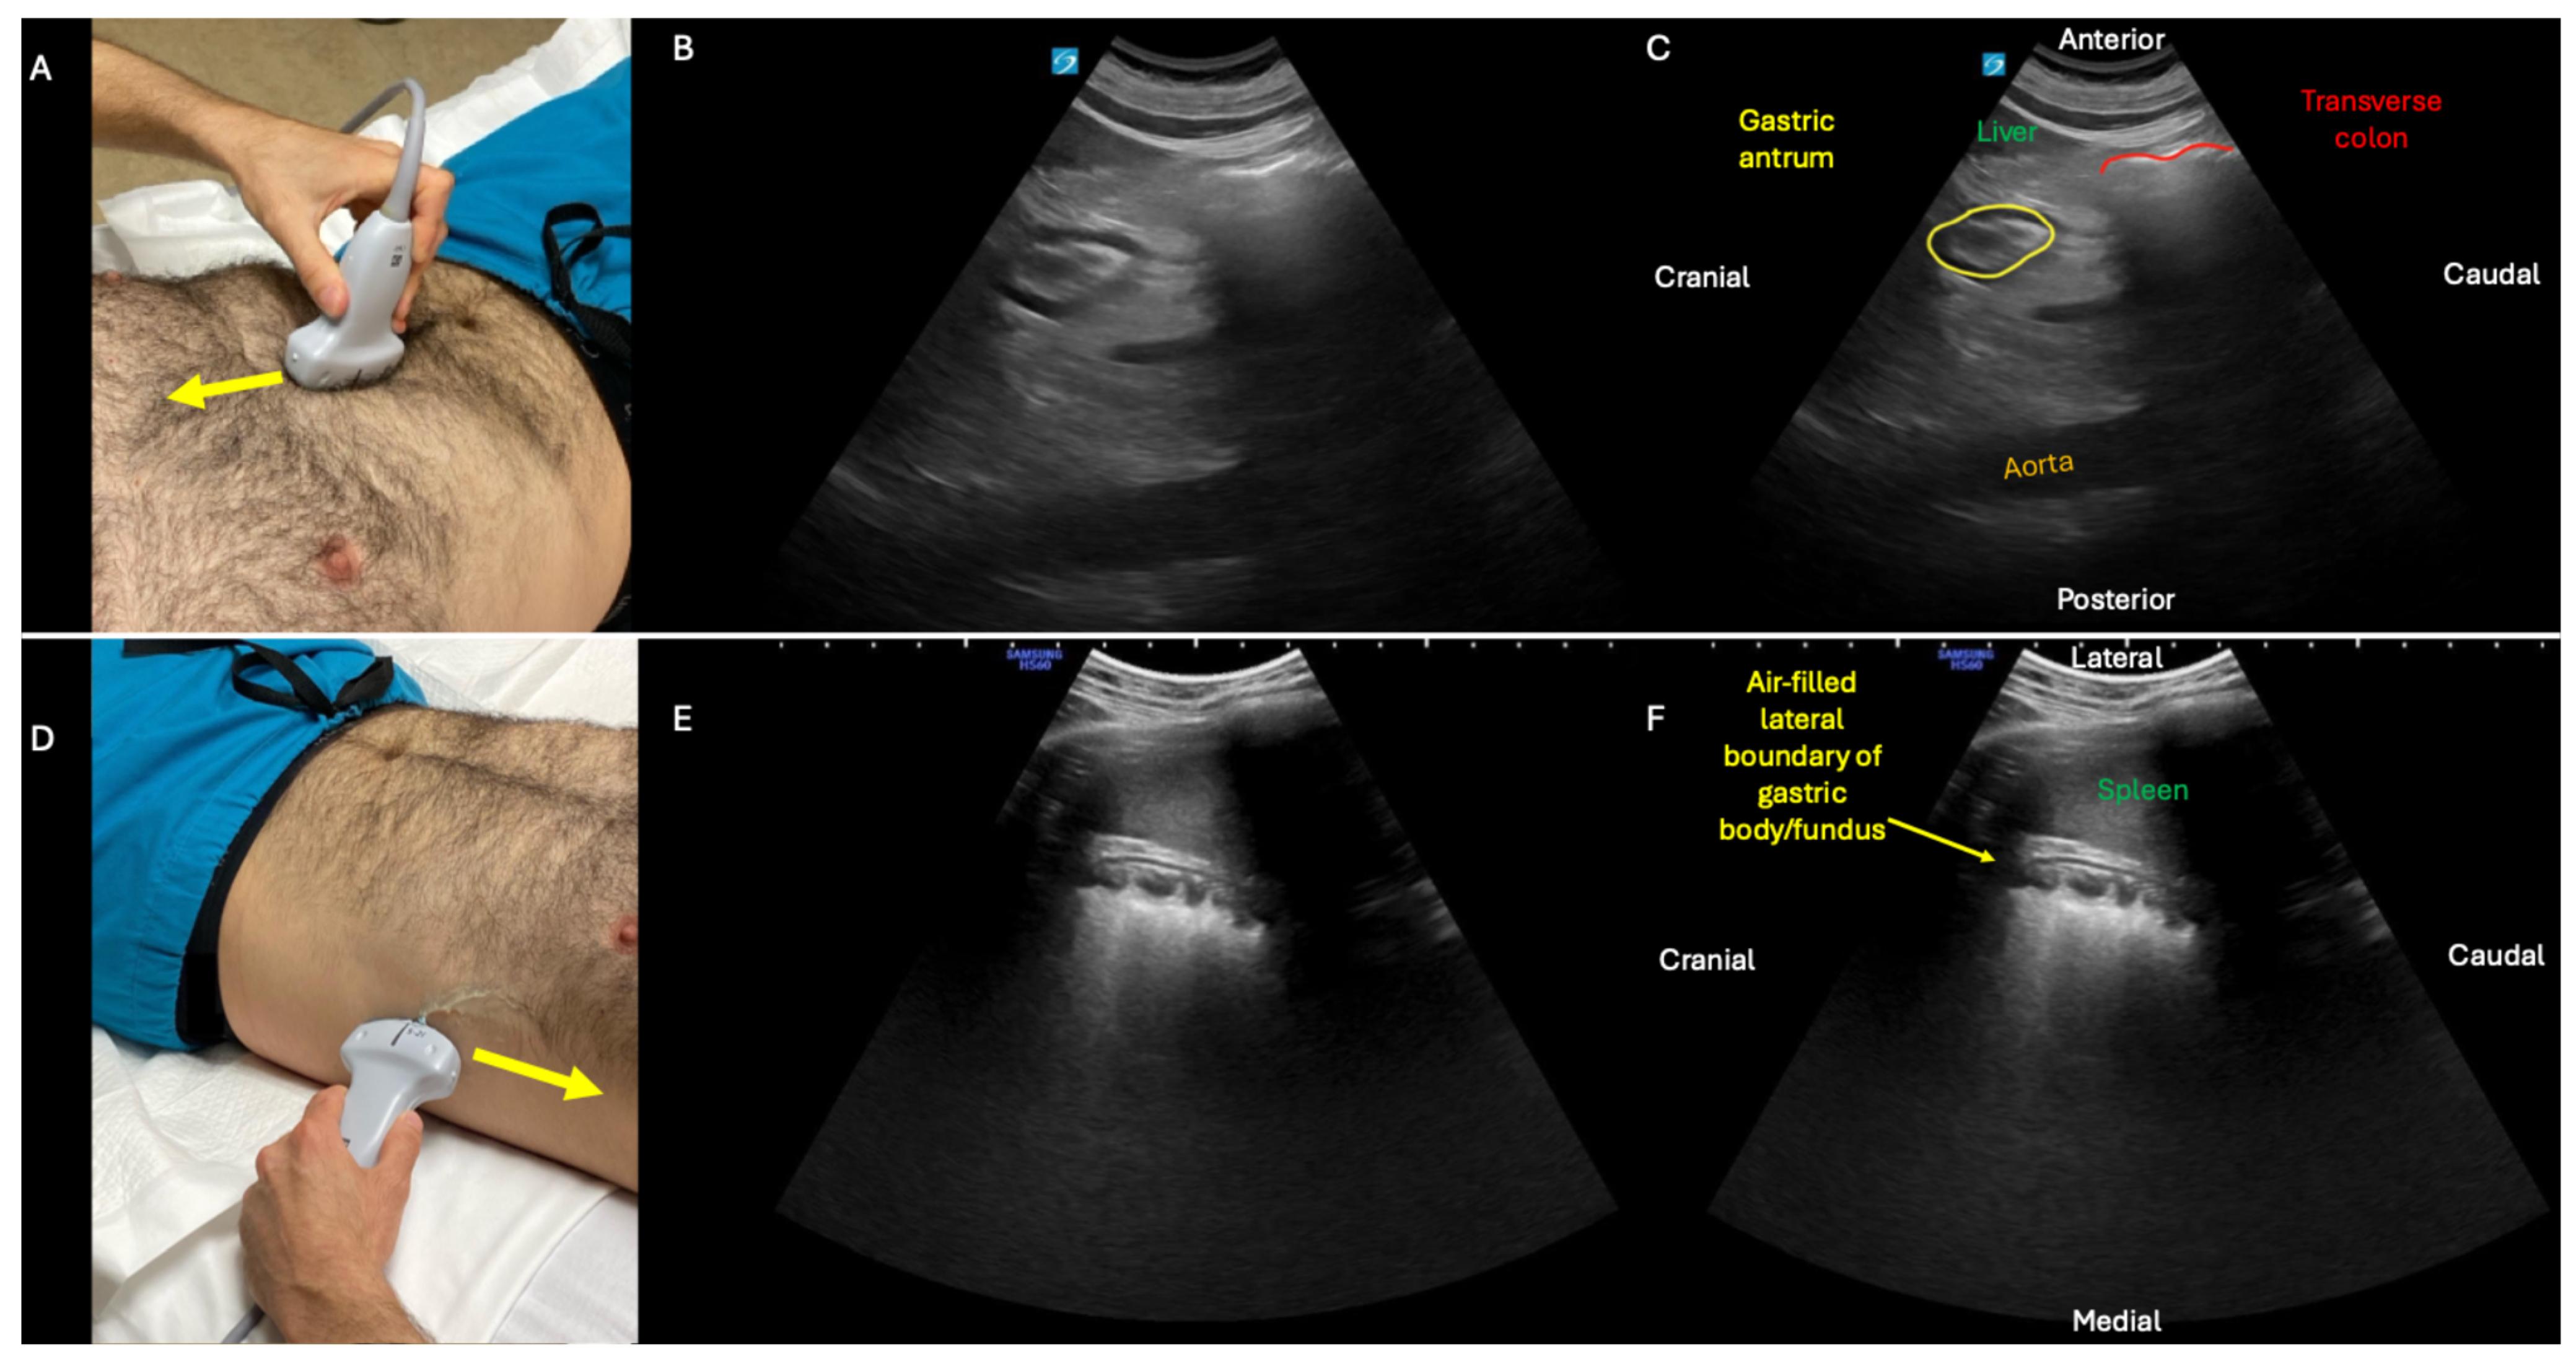

In the second phase of the GI POCUS protocol, two gastric ultrasound views are obtained: subxiphoid and left upper quadrant (LUQ). Top panel: subxiphoid view obtained with low-frequency, curvilinear probe positioned in approximately the mid-sagittal plane just caudal to xiphoid process (A), with probe indicator pointing cranially (yellow arrow), and example of an antrum (B,C) with trace fluid and no gross solids. Although the subxiphoid view is initially performed with patient supine, the sensitivity of the exam for gastric distension is increased by turning the patient right lateral decubitus and repeating this view [9]. Bottom panel: LUQ view of gastric body/fundus obtained with probe placed along the left flank at approximately the mid-axillary line (D), probe indicator pointing cranially (yellow arrow), view centered on spleen, and probe angled anteriorly to visualize stomach body/fundus rather than kidney (which can be visualized with this same probe positioning but with probe angled posteriorly). In this LUQ view, when the stomach is empty, the typical findings are acoustic shadowing within the body/fundus (E,F) due to the normal presence of air in the stomach (see also Supplementary Video S2; contrast with Figure 7 and Supplementary Video S7 showing gastric distension). By combining intestinal (Figure 1) and gastric (Figure 2) ultrasound, this two-phase protocol generates data that can help sort patients into categories of normal versus abnormal function of the stomach, small bowel, and—to a lesser degree—large bowel (see Figure 8).